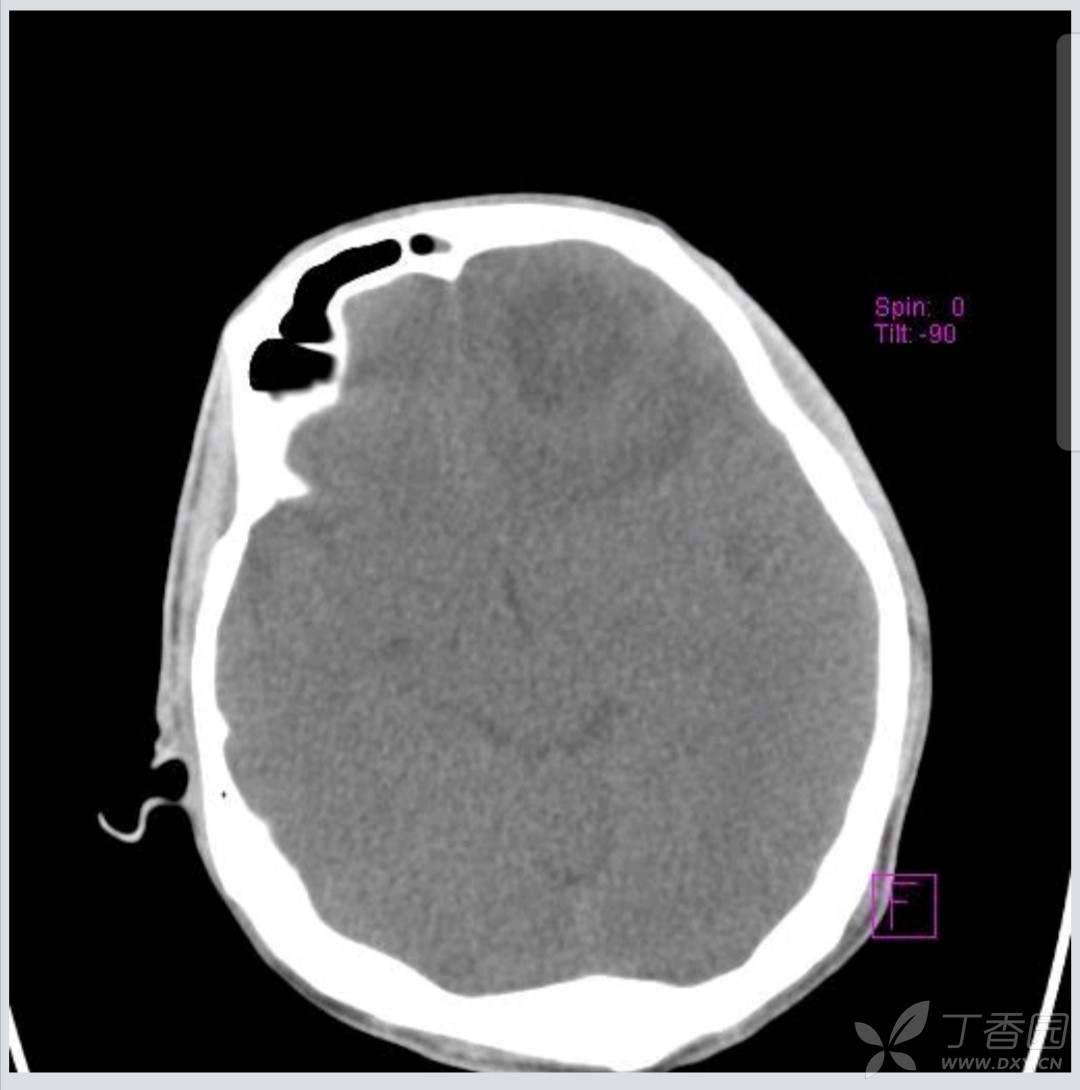

截取关键层面。两次大概在同一水平上。

抽搐后CT截取如下